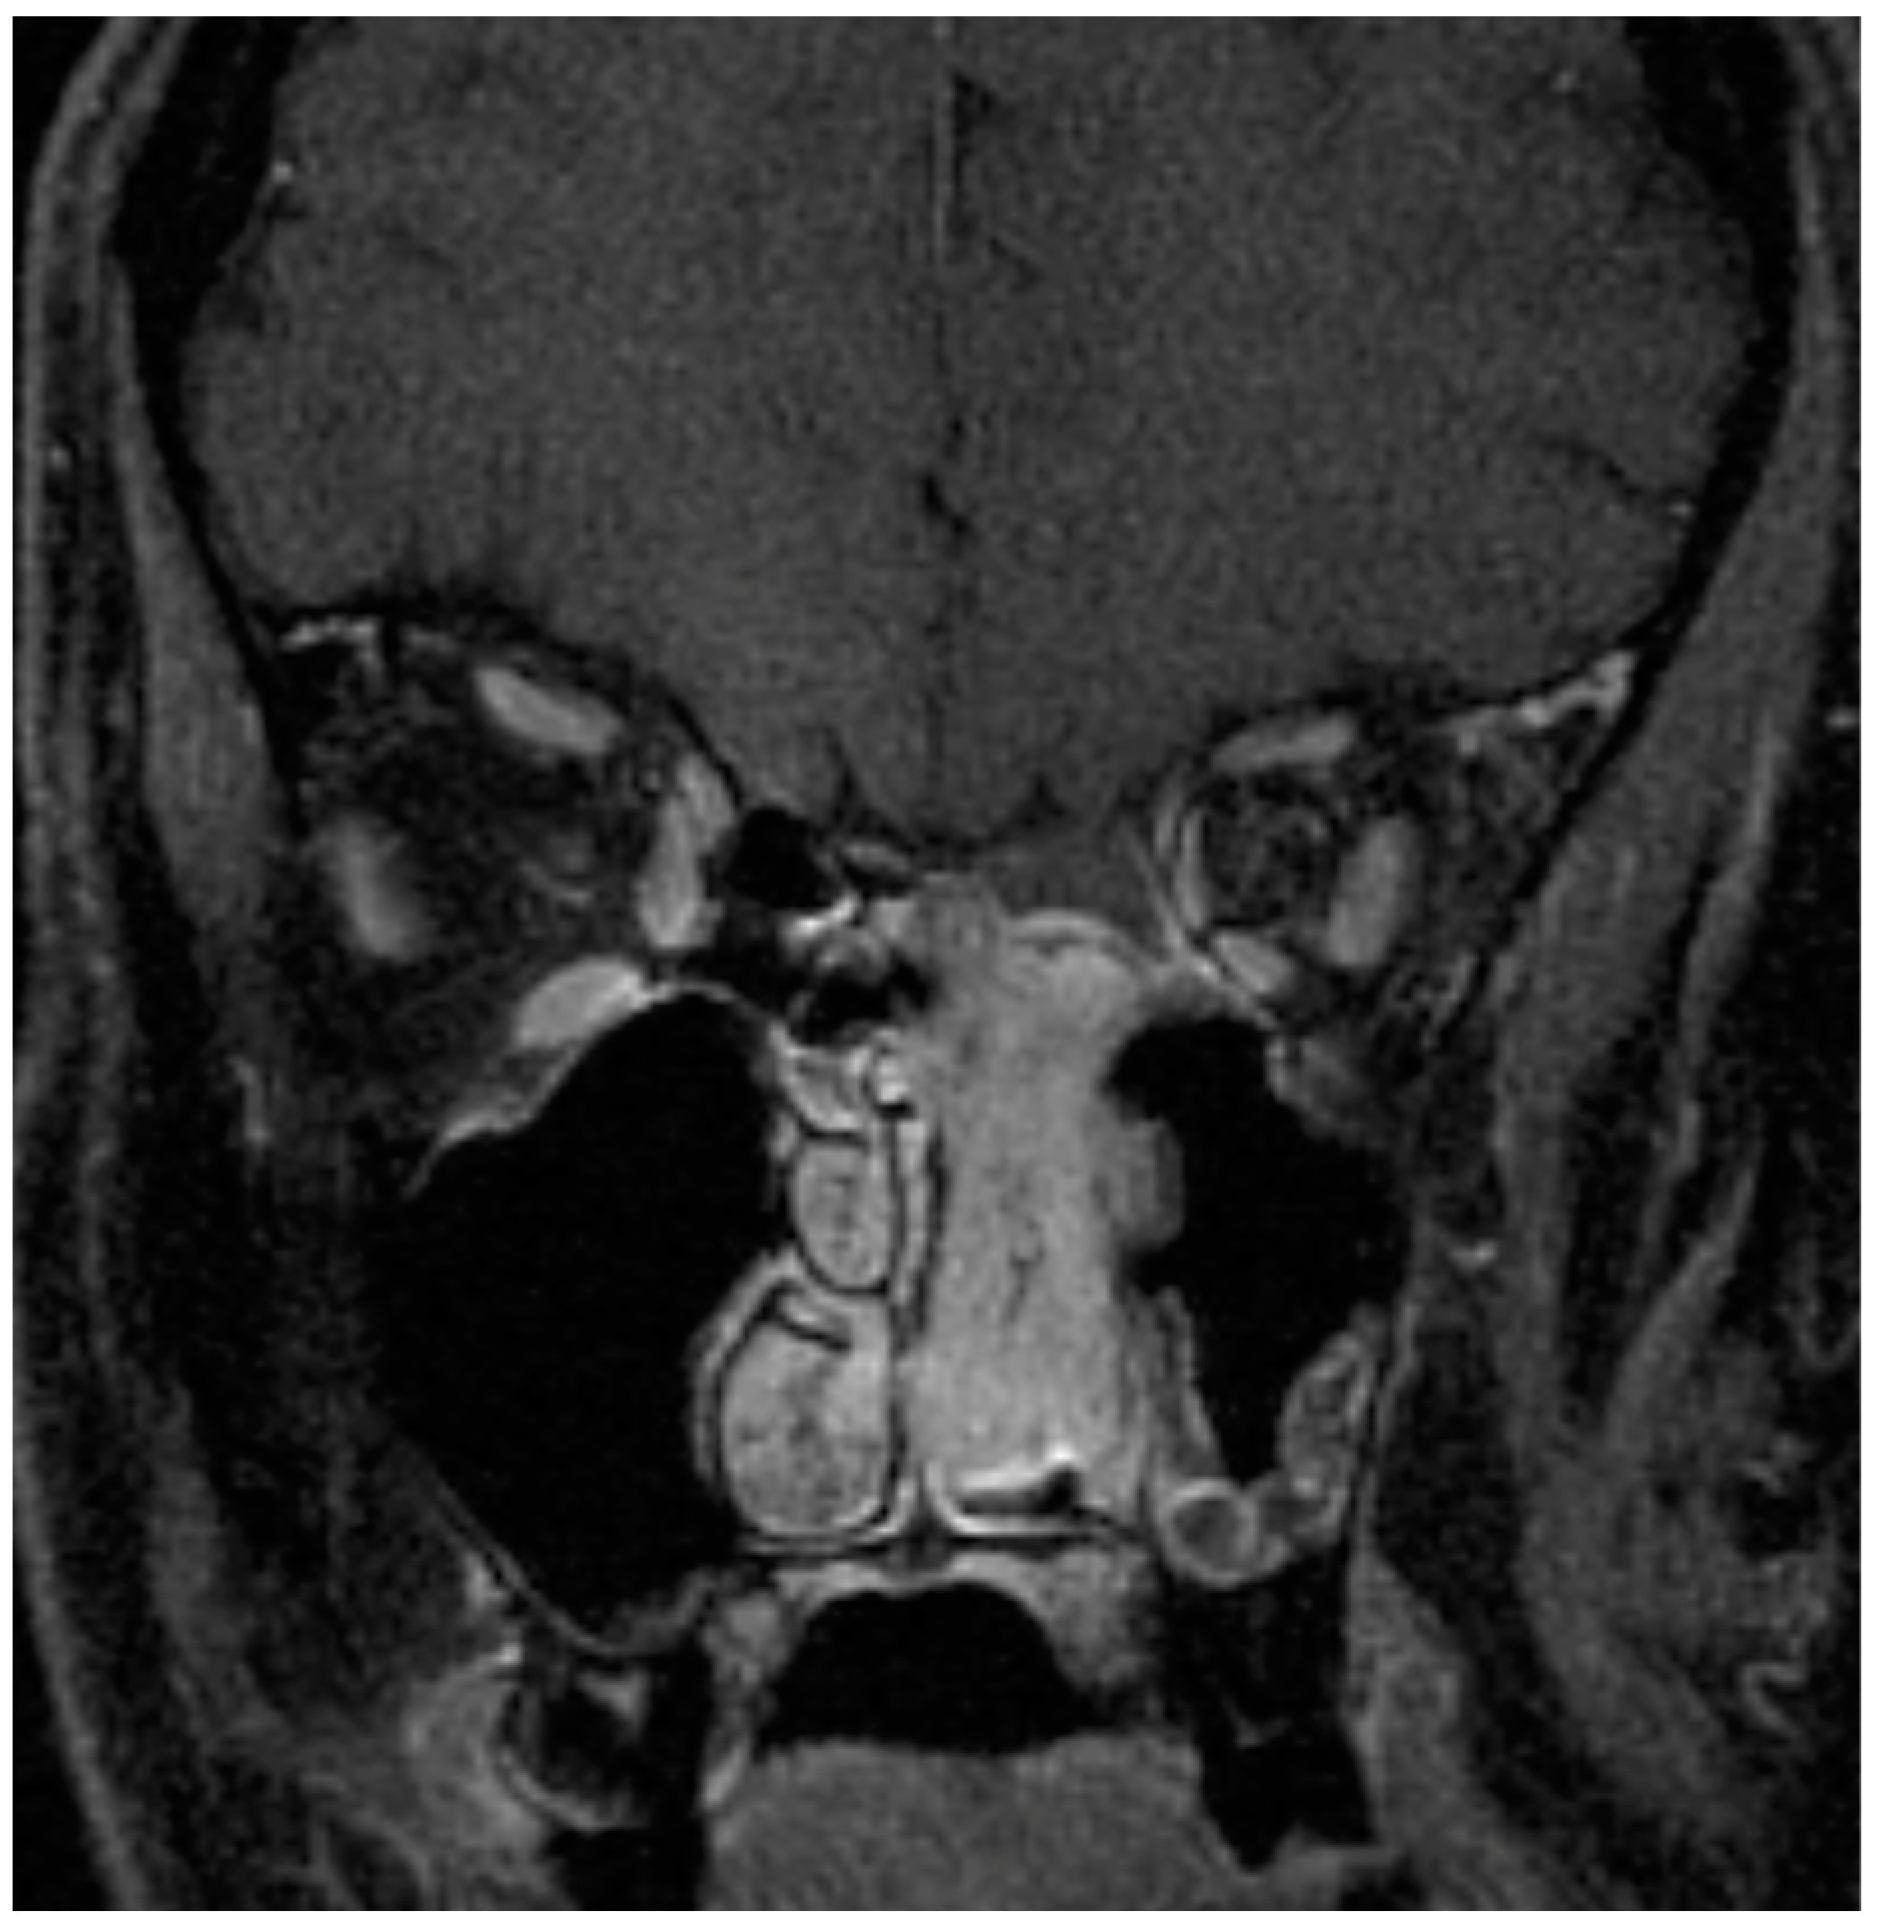

2. Patient- and Tumor-Specific Factors

- Geltzeiler, M.; Choby, G.W.; Ji, K.S.Y.; JessMace, C.; Almeida, J.P.; de Almeida, J.; Champagne, P.O.; Chan, E.; Ciporen, J.N.; Chaskes, M.B.; et al. Radiographic predictors of occult intracranial involvement in olfactory neuroblastoma patients. Int. Forum Allergy Rhinol. 2023, 13, 1876–1888. [Google Scholar] [CrossRef] [PubMed]

- Dublin, A.B.; Bobinski, M. Imaging Characteristics of Olfactory Neuroblastoma (Esthesioneuroblastoma). J. Neurol. Surg. B Skull Base 2016, 77, 1–5. [Google Scholar] [CrossRef] [PubMed]